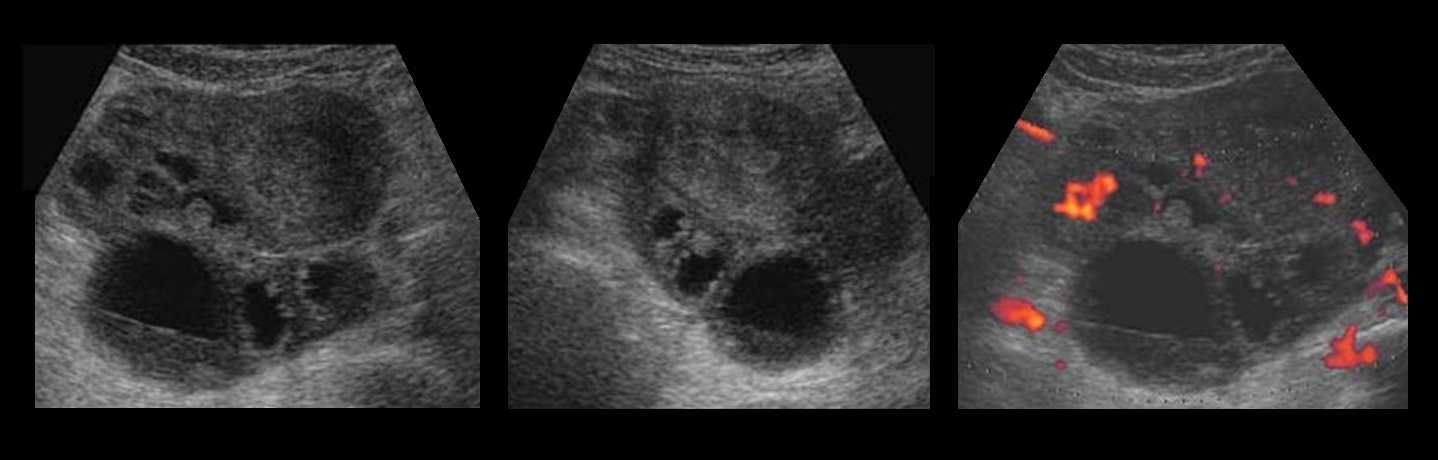

Злокачественные кисты при УЗИ обычно отличаются от доброкачественных по внешнему виду: в них больше полостей, выступов внутри кисты, они частично жидкие, частично твердые и т. д. При малейшем подозрении на злокачественную кисту с помощью обычного УЗИ, проводятся исследования кровотока через кисту. Рекомендуется цветное допплеровское ультразвуковое исследование и определение онкомаркеров в крови (CA 125, CA 19-9, CAE, beta HCG, HE 4, индекс ROMA). Следует отметить, что обе процедуры имеют свои ограничения.

Рисунок. На УЗИ многокамерная кистозная масса с волнистым контуром, содержимое гипо- и анэхогенное, стенки местами утолщены — солидные компоненты. Заключение: Муцинозная цистаденома.